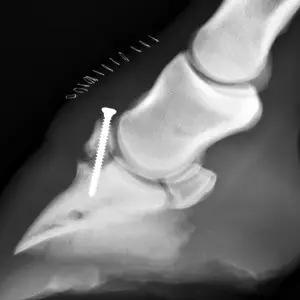

Hufbeinfrakturen stellen aufgrund der Lokalisation des Hufbeins innerhalb der Hornkapsel des Hufes eine chirurgische Herausforderung dar. Frakturen im Hufbeinastbereich werden mit Boxenruhe, Spezialbeschlag und Hufgips behandelt. Längsfrakturen des Hufbeines haben wegen der Gelenkbeteiligung und dem daraus resultierenden Arthroserisiko eine ungünstigere Prognose und können wahlweise verschraubt oder mit Gips behandelt werden.